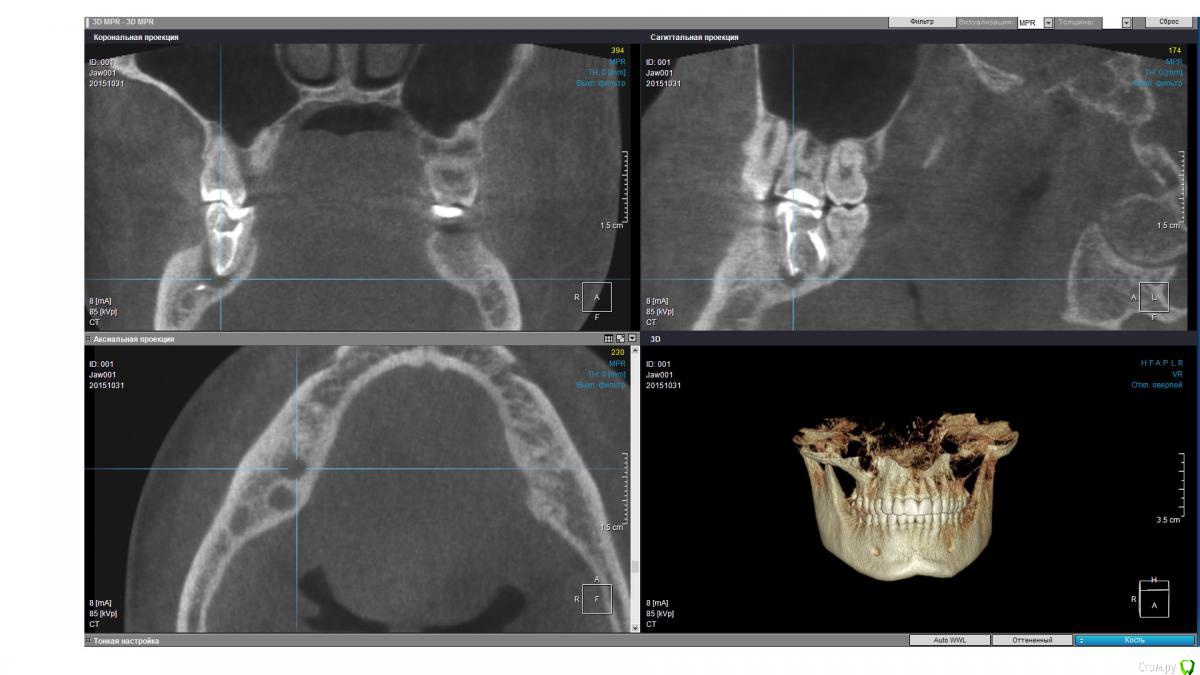

isubru Опубликовано 31 октября, 2015 Поделиться Опубликовано 31 октября, 2015 (изменено) Здравствуйте, Депульпировали зуб, потом он болел где-то с год. Больно было сильно надкусывать, потом боль прошла. "Смеркалось". Через какое-то время на десне сформировался "гноепровод". Постоянно что-то течет. Зуб предлагают удалять (должен сказать, что эта процедура настолько тут в ходу, что на неё всех поголовно отправляют). Сделал КТ. Под 47 действительно 2 кисты, но что интересно на дне полостей какие-то плотные нитевидные "обломки" в 2.5-2.8мм длинной и 1мм в диаметре. Буду очень признателен совету, как мне избавится от этой напасти. Зуб, видимо, уже не спасити?31 ноября 2015 Чуть менее годом ранее. Изменено 31 октября, 2015 пользователем isubru Ссылка на комментарий

DmitrySH Опубликовано 31 октября, 2015 Поделиться Опубликовано 31 октября, 2015 Если только на основании данного КТ, то есть шансы и спасти.На КТ фрагментов инструмента не увидел. Есть какие-то точки. Но надо понимать, что пломбировочным материал, инструменты и тп в каналах сильно "фонят" на КТ. Прицельные снимки есть? Ссылка на комментарий

isubru Опубликовано 31 октября, 2015 Автор Поделиться Опубликовано 31 октября, 2015 (изменено) Да, был. Нужно поискать. Только там в принципе тоже самое. Одна киста, что между 46 и 47 слабо различима в той проекции, хорошо видно только ту, что под другим корнем. PS. Прикрепил в 1й пост. Относительно точек, вряд ли это артефакт (только 2 специфических места на всей CT). Да и на прицельном снимке они есть. Какова вероятность, что они могли быть причиной образования кист(к примеру, механическое повреждение ими при надкусывании на этом зубе)? Изменено 31 октября, 2015 пользователем isubru Ссылка на комментарий